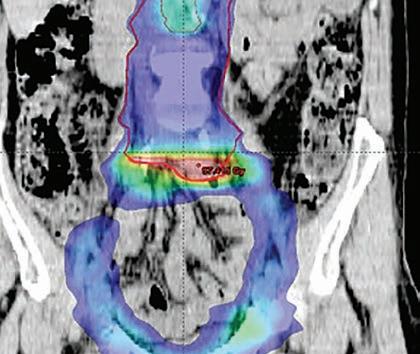

Medical Physics is the branch of physics that applies the concepts and principles of physics to the diagnosis and treatment of human disease. The MSc in Medical Physics is designed for students who wish to pursue a career in Medical Physics, either in a clinical environment or in research.

The programme provides a strong foundation in diagnostic imaging physics, nuclear medicine, radiation oncology physics and radiation protection, as well as the essential anatomy and physiology knowledge required to understand a patient’s anatomical structure and physiological processes.

Images © UCD Research early online at www.ucd.ie/apply